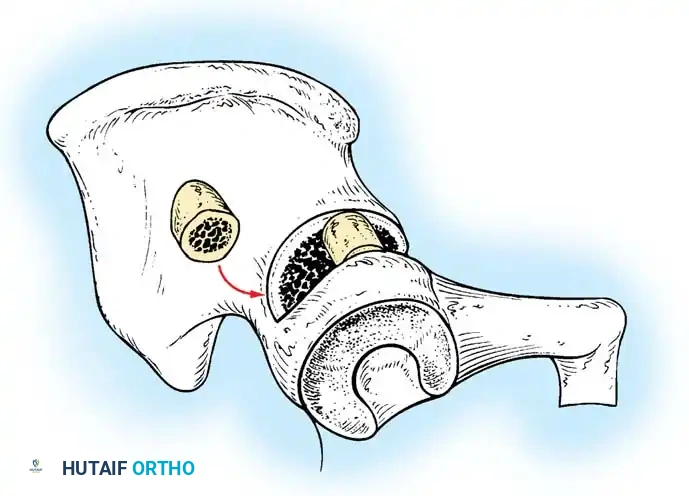

3. Arthrogram: Dye is injected to visualize the cartilaginous profile. Look for the "rose thorn" sign (limbus), the transverse acetabular ligament, and the ligamentum teres. Pooling of dye medially indicates an interposed pulvinar or inverted limbus preventing concentric reduction.

Intraoperative arthrogram demonstrating the cartilaginous contours of the femoral head and acetabulum during closed reduction.